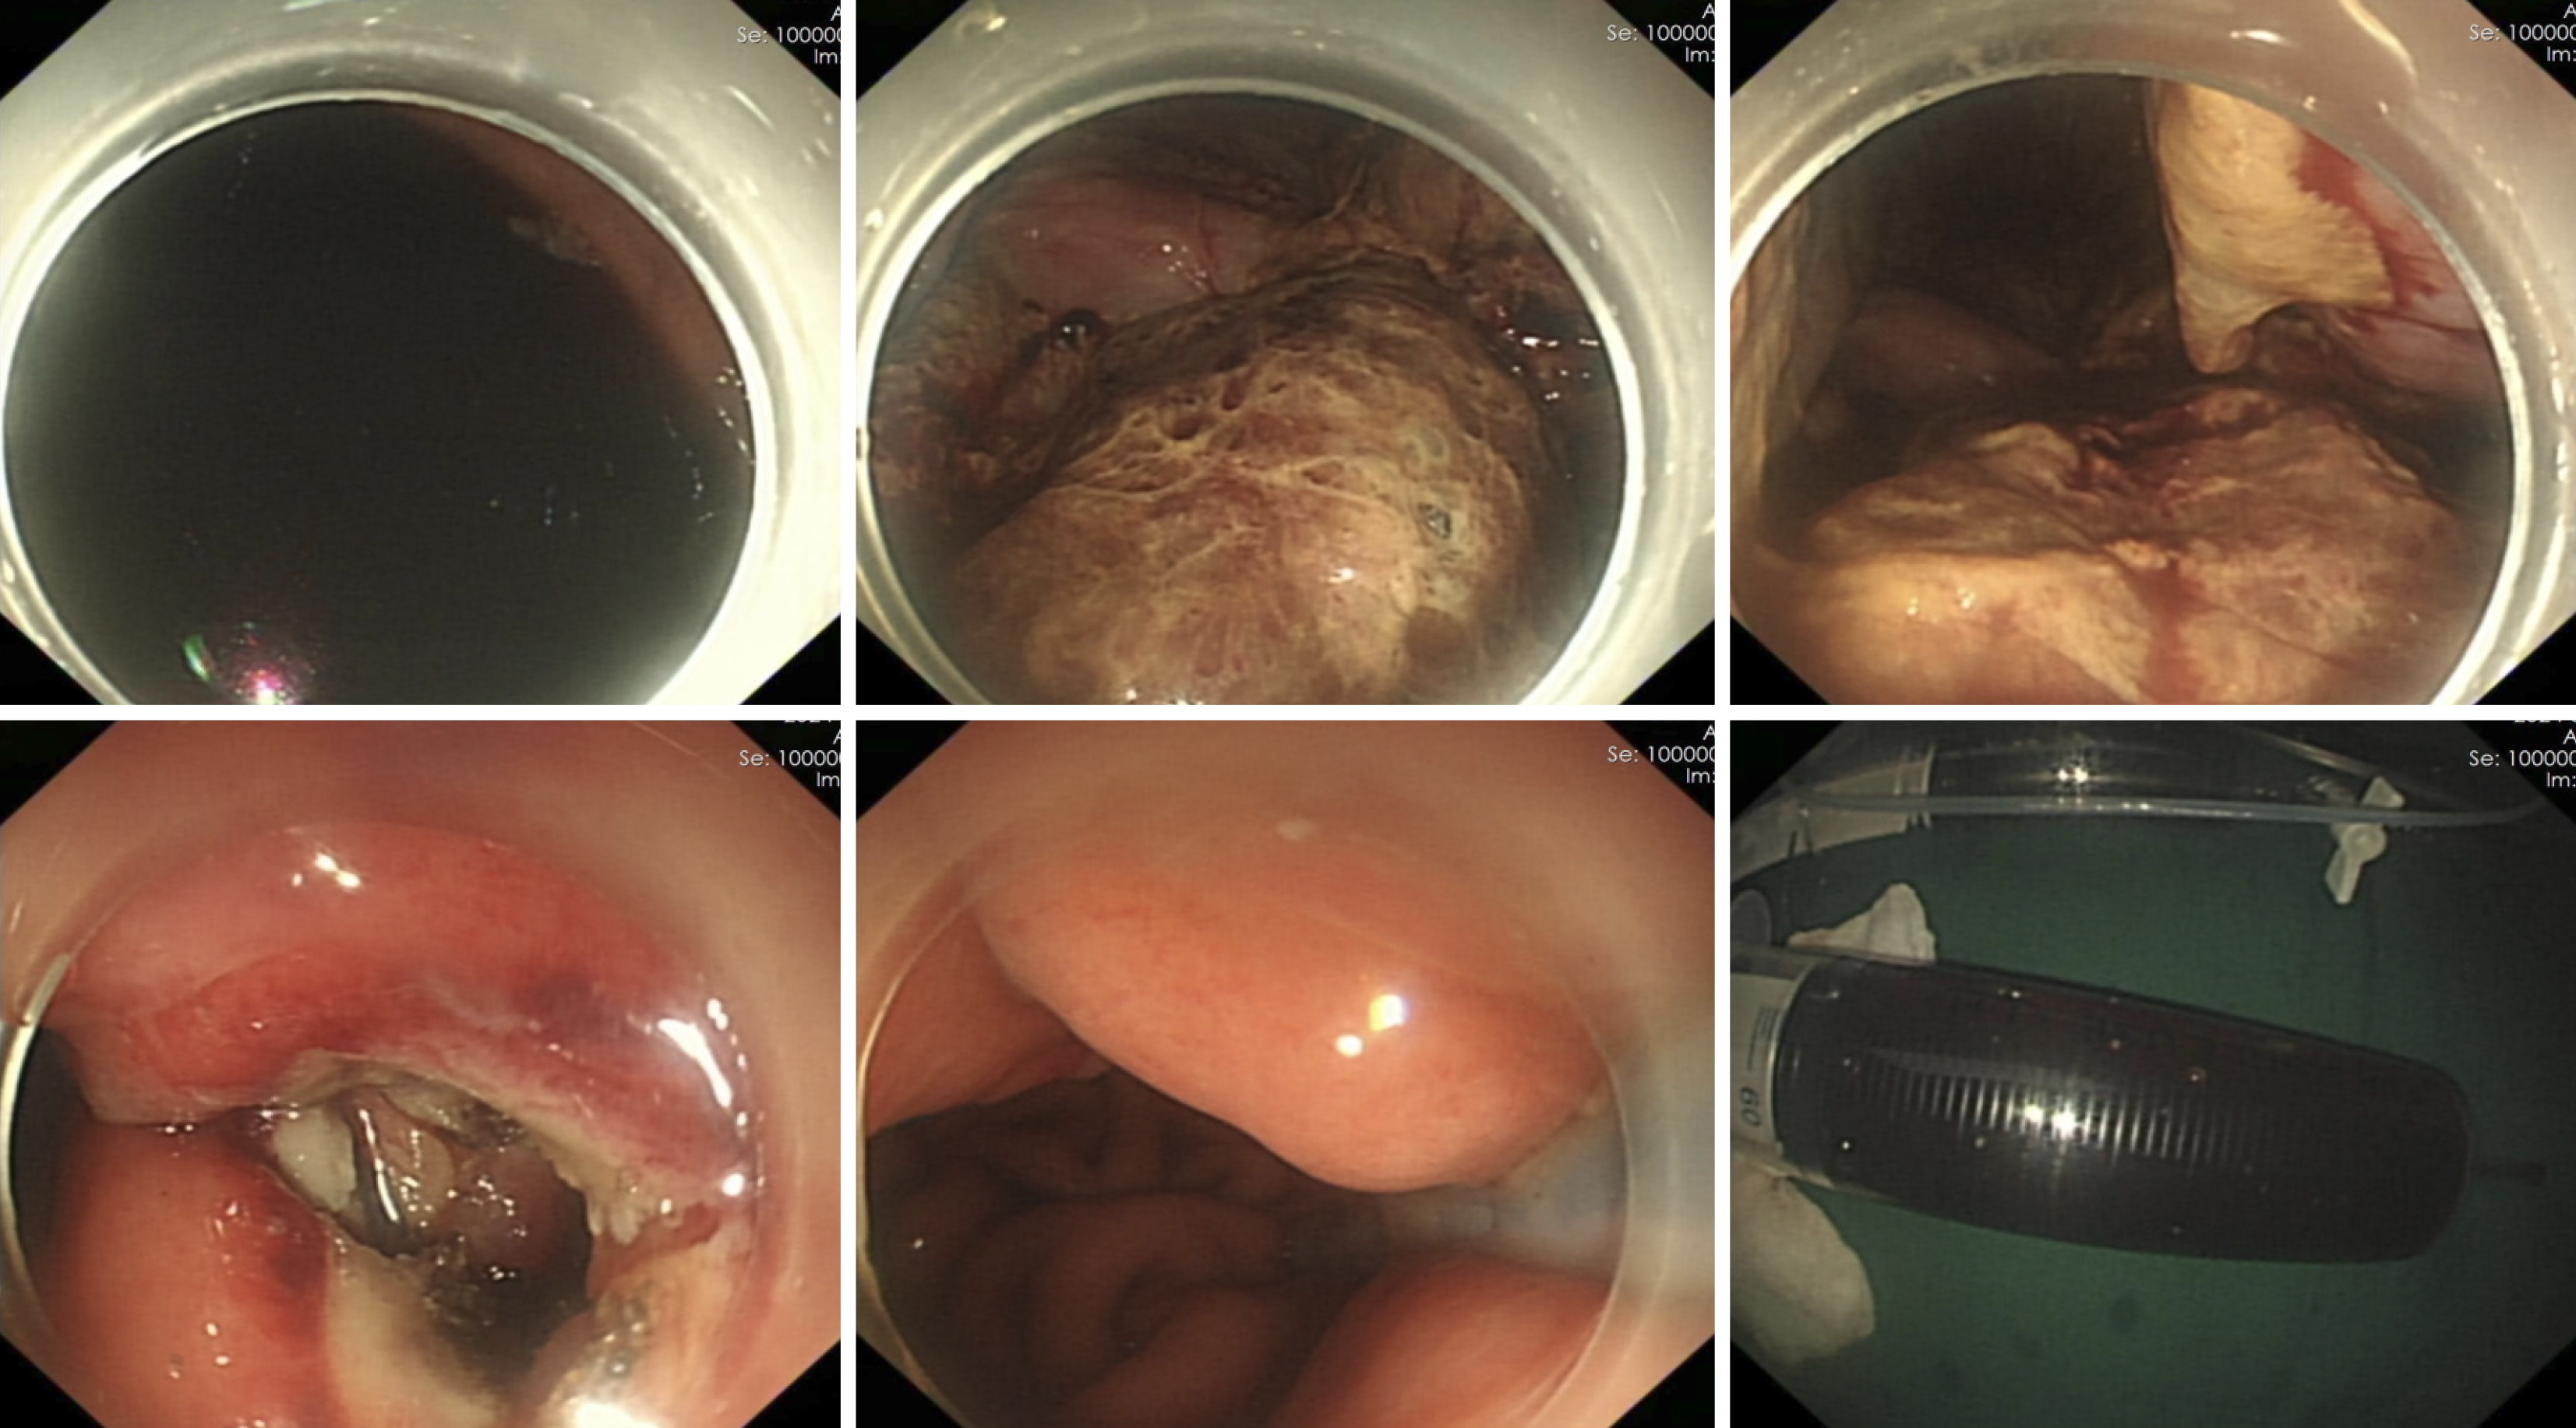

Under general anesthesia with endotracheal intubation, endoscopic ultrasound revealed a circular hypoechoic lesion in the body of the pancreas, with scattered areas of increased echogenicity (Figure 2). A 23G needle was utilized for puncture, yielding a coffee-like fluid. The puncture site was marked, and a Dual knife was employed to incise the gastric wall, exposing white, wall-like tissue. Upon aspiration with the puncture needle, a significant amount of coffee-like fluid was observed, prompting a deeper incision at the site, resulting in a substantial outflow of fluid (Figure 3). The endoscope was subsequently inserted into the cystic cavity to facilitate further aspiration, revealing a flocculent substance at the base. Hemostasis was achieved, and a gastric tube was placed (Figure 4).

Post-procedure imaging via CT scan, conducted eight hours after the endoscopic intervention, demonstrated complete resolution of the pancreatic cyst (Figure 5A). A follow-up CT scan on the sixth postoperative day indicated the re